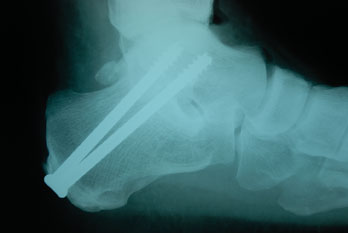

One can facilitate successful fixation of the fusion site via numerous methods. The most common method is screw fixation. Arthrodesis of the subtalar joint as part of a triple arthrodesis only requires one point of fixation. The fixation of the other joints of the hindfoot complex prevents motion of the subtalar joint so a single screw may suffice. For an isolated subtalar arthrodesis, two points of fixation are recommended.12 Use one screw to compress the posterior facet of the subtalar joint while a second point of fixation prevents rotation.

One may insert the primary fixation screw from the talar neck through the posterior facet and into the calcaneus, or from the posterior plantar calcaneus across the posterior facet and into the talar body. The disadvantage of the primary screw placement from the talar neck down into the calcaneus is potential neurovascular injury and anterior ankle impingement. It is generally not possible to orient this screw perpendicular to the posterior facet.

I prefer utilizing two large cannulated screws from the calcaneus into the talus through one incision. Insert the first screw from the posterior plantar calcaneus and direct it into the body of the talus. This screw compresses the posterior facet of the subtalar joint.

The second screw is slightly more medial and one should direct it more distally in the talar body or neck. This screw prevents any rotation about the first lag screw. Another option for a second screw is to insert it from the lateral process of the talus into the calcaneus. The fixation for a distraction bone block arthrodesis of the subtalar joint involves fully threaded screws or screws with threads that traverse the host graft interface. Do not use the lag technique as the purpose of the screws is to maintain the distraction and prevent collapse of the graft. Employ the same screw orientation from the calcaneus into the talus.

One must use intraoperative fluoroscopic imaging to demonstrate ideal alignment and the position of the fixation. Use lateral imaging of the hindfoot/ankle to assess the talocalcaneal relationship as well as the screw position and length. A dorsal to plantar view of the foot enables one to assess the talocalcaneal angle, midtarsal alignment and the talus to first metatarsal alignment. Surgeons should also obtain ankle mortise views to confirm position of the screws in the talar body and neck. Avoid a common malposition of the lateral screw into the lateral gutter of the ankle joint.